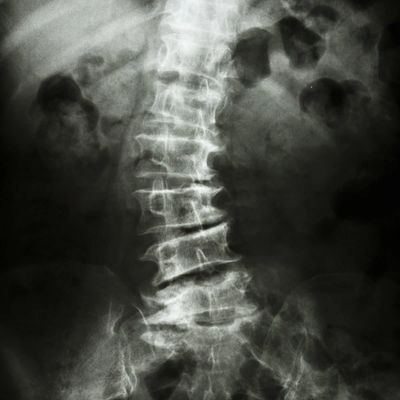

MAIC digital xray will allow your doctor to review your xrays in seconds, giving MAIC clearer images, precise reads, and fewer retakes. All of this is stored in our HIPAA-Compliant cloud storage as well as onsite in our PC.

It will allow the Clinic to discuss Cervical, Thoracic and Lumber curves with the ability to compare and contrast previous x-rays on a split screen. The Doctor will be able to analyze the Atlas angle and axis. The clinic will also be able to burn discs for their patients.

Improves the ability to diagnose, treat and communicate with our patients. Produce diagnostic-quality images in seconds, then annotate! Create an auto-generated RAD Report